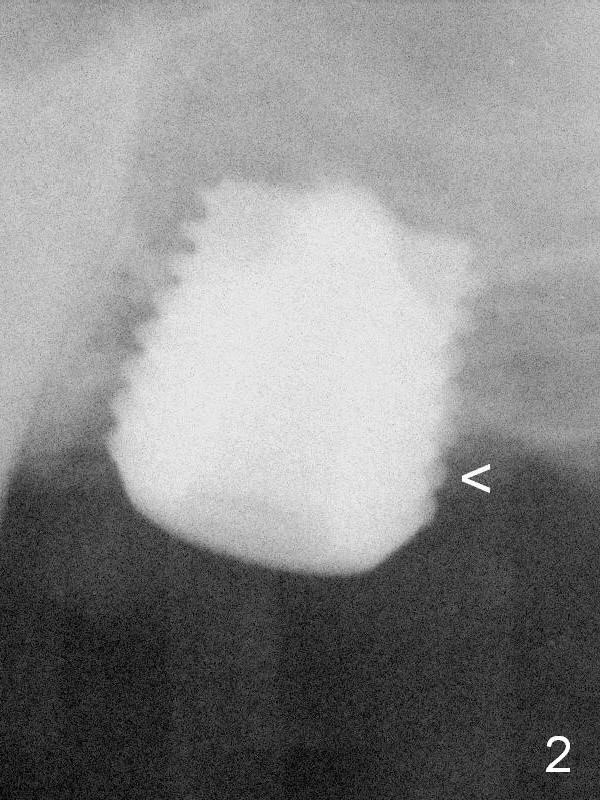

The implant is backed up and re-directed. The trajectory is changed within normal limit (Fig.2); the torque is slightly less than before. The distal 2nd thread is outside the crestal bone (<).